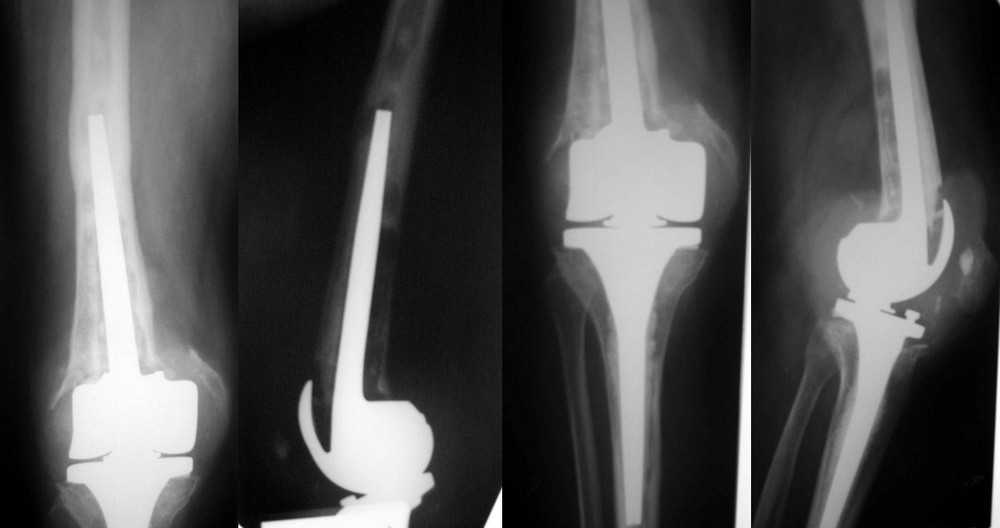

Пациентка 72 лет. Асептическая нестабильность бедренного компонента ротационного протеза Endo-Model (Waldemar Link).

Тибиальный компонент наиболее вероятно стабилен по данным R-графии. Индивидуальный эндопротез у W.Link оказался неподъемным по цене. Уважаемые коллеги, подскажите где и у какой фирмы можно найти соответствующий имплантант, оптимальный по цене - качеству.